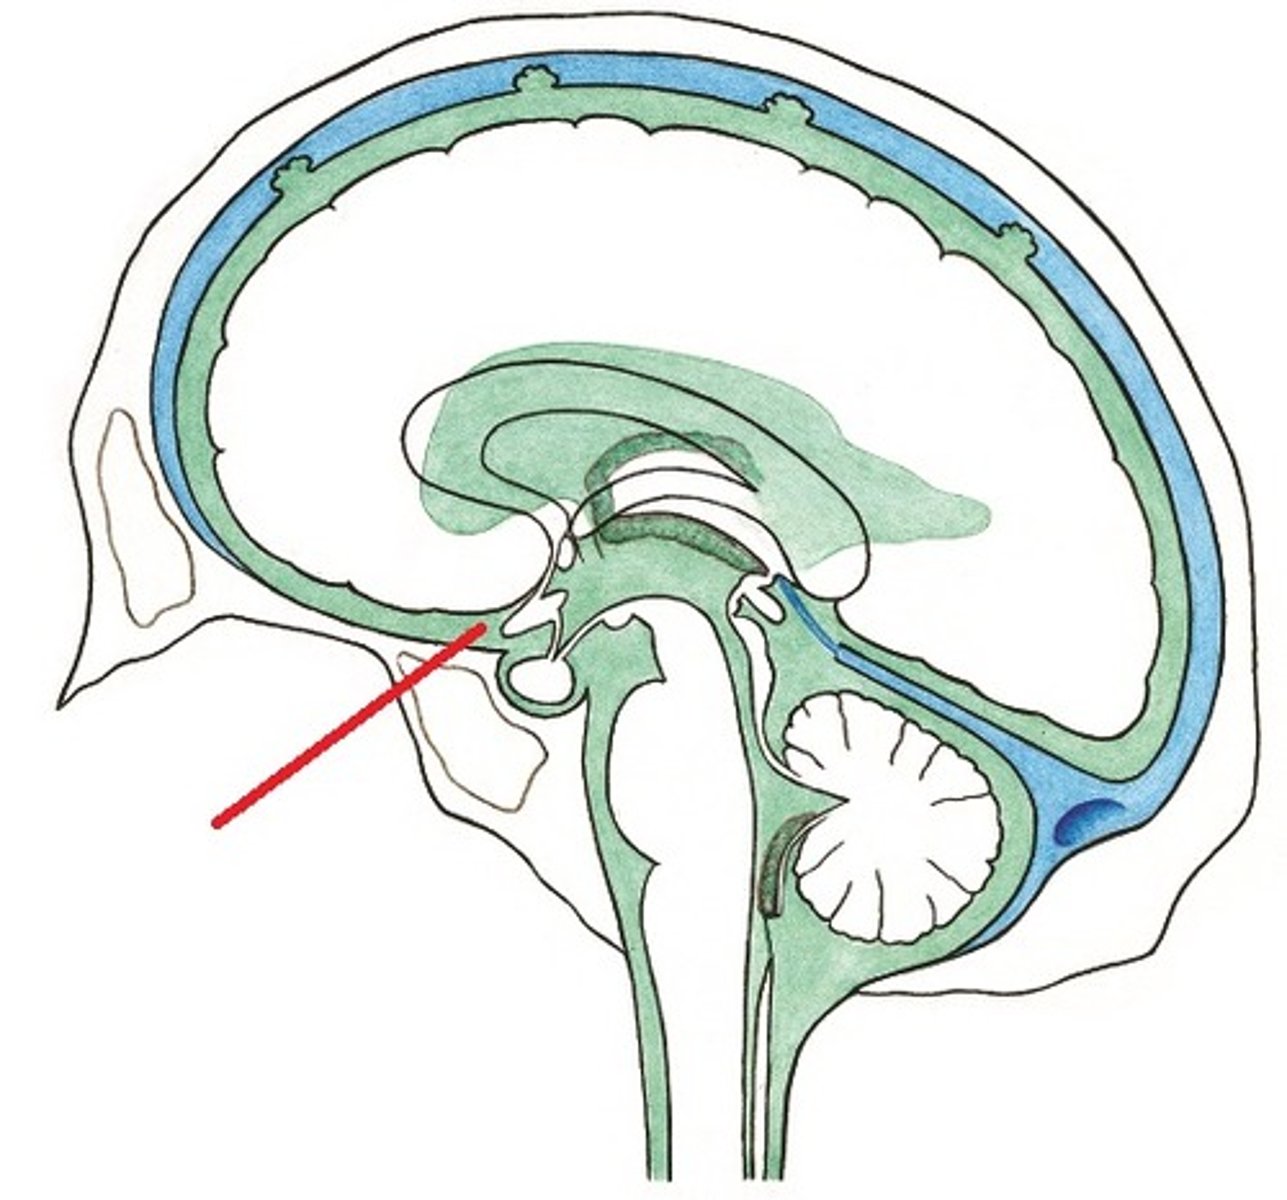

cervicomedullary junction

transition between the medulla oblongata and upper cervical spinal cord (C1-C2) that is located at the level of the foramen magnum

*houses ascending/descending tracts (decussation) and nuclei that influence breathing, CV control, and CN 9-12

*orange line on picture

tentorium cerbelli

horizontal meningeal fold of the dura mater that separates the cerebellum from the occipital lobe

*contains passage for brainstem (tentorial notch)

structure that connects the third and fourth ventricles, and is located at the midbrain

*vulnerable to obstruction due to narrow nature

*common cause of non-communicating hydrocephalus